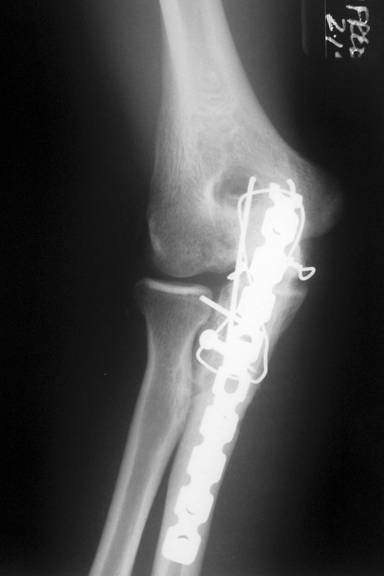

AC is a 25 year old male who was assaulted with a baseball bat. He sustained a shattered proximal ulna fracture with elbow dislocation. Surgery required application of a plate and screws, as well as pinning and cerclage wiring. He worked diligently in therapy to regain the excellent range of motion in his elbow as demonstrated in the photo with me.